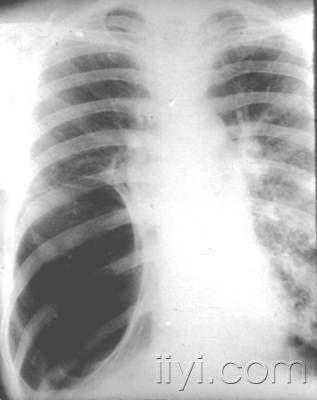

它让医生终于能“纵观全局”了。以前看脊柱侧弯,得靠拍好几张片子在脑子里想象拼接,现在一张全脊柱正侧位片,弯了多少度(Cobb角)、主要弯在哪儿,一目了然-2-7。对于需要做关节置换(比如换膝盖、换髋关节)的病人,术前拍一张双下肢全长拼接片,医生就能精准测量你的下肢力线、关节角度,为安装假体设计出最符合你个人生物力学的方案,这可是手术成功、让假体用得长久的基石-2-9。

它更真实。很多检查可以让你站着拍(立位负重位),这就模拟了你平时走路、承重的真实状态。在这种状态下呈现的脊柱曲度、关节间隙狭窄和畸形,比躺着拍更有诊断价值-7。